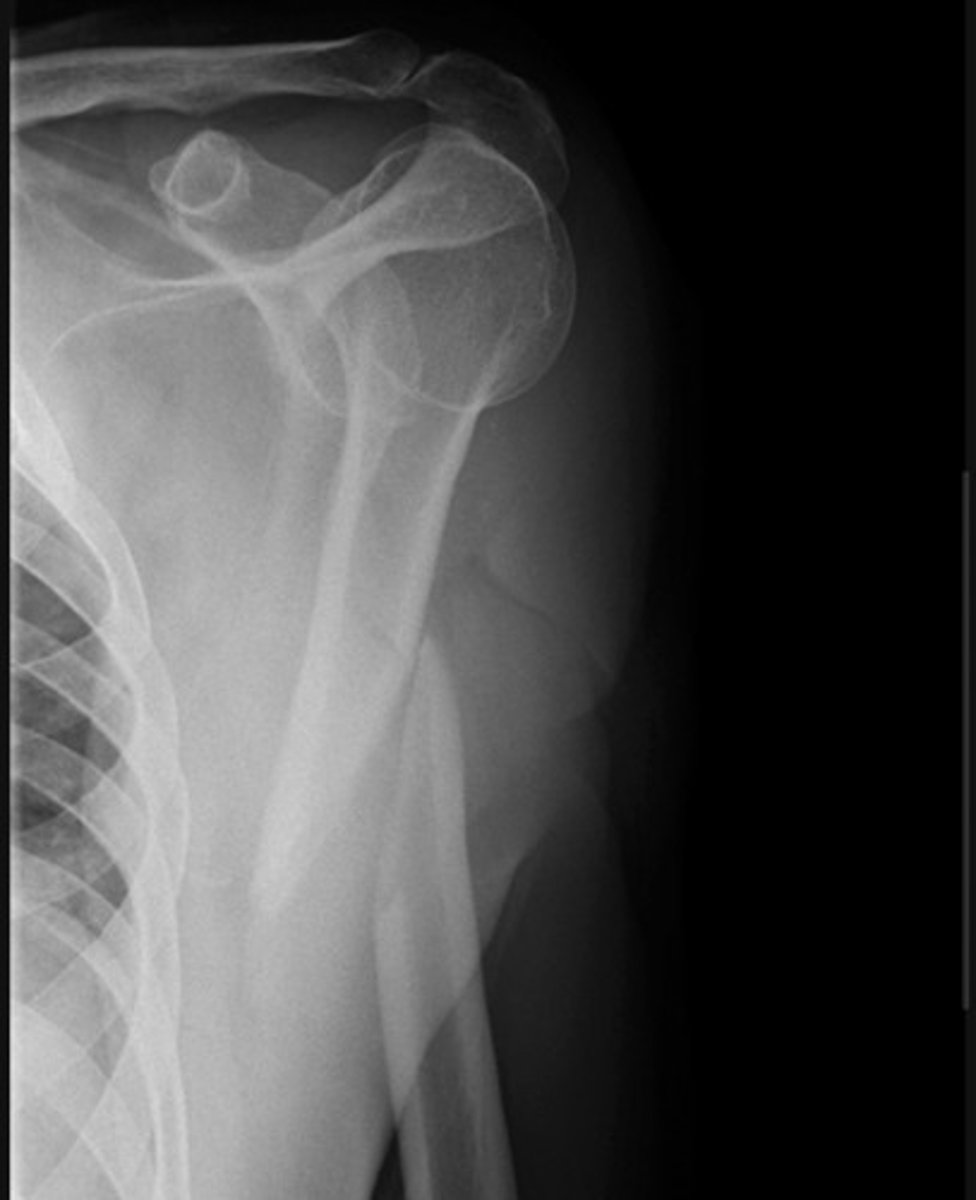

Surgical neck fracture-

Transverse fracture through the proximal humerus with displacement of the distal component